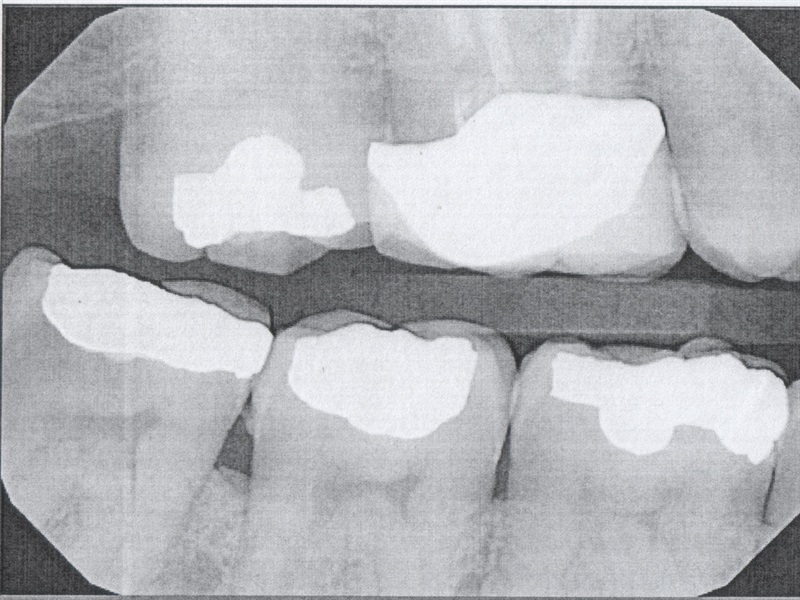

Bruxism and Beyond: Managing Teeth Grinding with a Multifaceted Approach